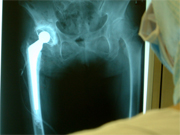

写真は、人工股関節の術後写真。手術シュミレーションシステムの術後評価機能の設計で前方開角の計算処理と操作手順を検討していた。